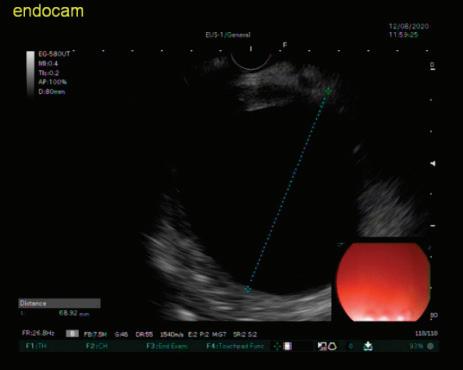

Доц. д-р Цветелина Тотомирова

48 КИСТИ НА ПАНКРЕАСАЗНАЧЕНИЕ, ДИАГНОСТИЧНИ ДИЛЕМИ И ИНДИКАЦИИ ЗА ХИРУРГИЯ Н. Шумка, П. Карагьозов

60 РАДИОФРЕКВЕНТНА АБЛАЦИЯ НА ПАНКРЕАСНИ ТУМОРИ ПОД ЕНДОСОНОГРАФСКИ КОНТРОЛ Й. Петкова, П. Карагьозов, И. Тишков УРОЛОГИЯ